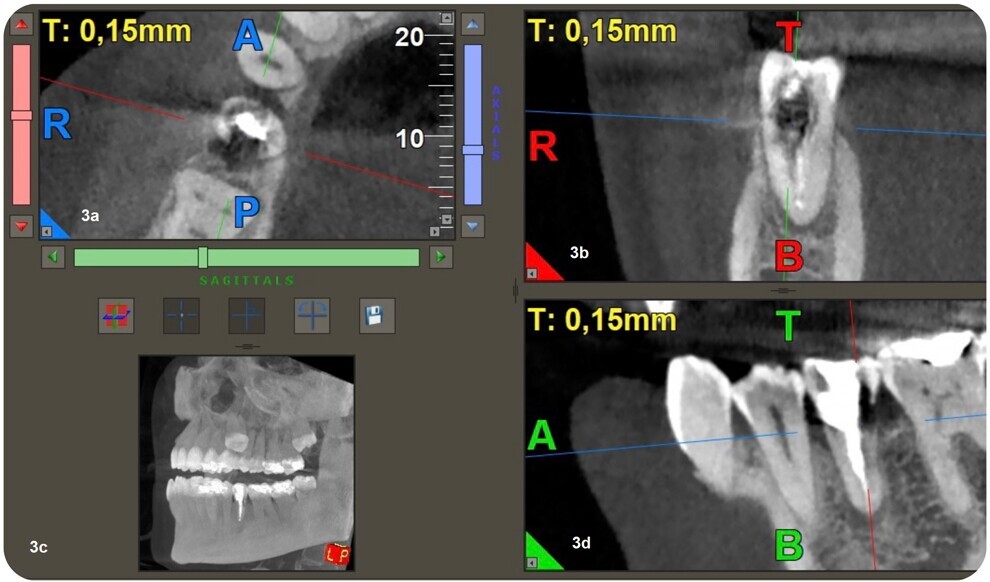

Figs. 3a–d: 3D reconstruction of axial section showing extension in mesial-distal direction (a). 3D reconstruction of a sagittal section showing the lesion extension, buccal-palatal direction (b). Coronal section of CBCT showing the extension of the periapical lesion and the resorptive defect (c). CBCT scan (d).

The radiographic examination showed periapical radiolucency and a radiolucent lesion in the cervical area of the tooth (Figs. 1 & 2). To determine the extent and depth of the lesion, a CBCT scan was performed (Fig. 3). Based on the CBCT images and 3D reconstructions, a diagnosis of Heithersay Class III external cervical invasive root resorption (ECIR) was determined in an endodontically treated tooth with symptomatic periapical periodontitis. The patient was informed of the diagnosis, treatment plan alternatives and prognosis of the case.

CBCT is a useful tool in endodontics, being used to assess the extent of an external cervical resorption defect, to detect and classify periapical periodontitis and to assess anatomical references with greater accuracy. Various studies have proved that CBCT is very helpful in diagnosis of this type of resorption.2–4 In the clinical case presented, an apical lesion and ECIR were observed, and CBCT was used to observe the size of the periapical lesion and the size and location of the resorption defect at the three spatial levels.